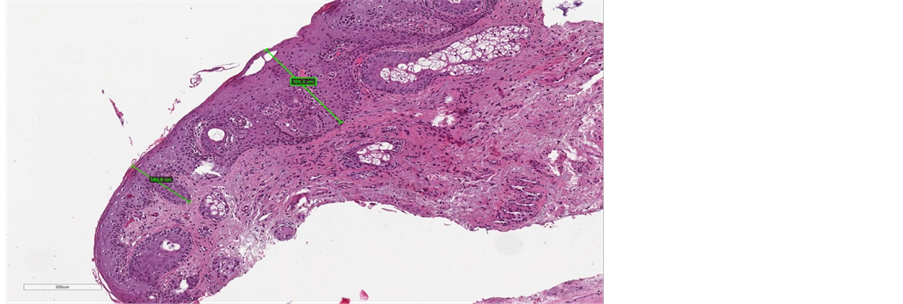

Before treatment, the stratified squamous epithelium appeared atrophic and thin, with no evidence of the crests of the Malpighian layer and epithelial papillae, and with a flattened sub-epithelial junction (Figure 4(a), Figure 5(a), Figure 6(a)). Post-treatment histology samples showed restoration of the epithelial and subepithelial structures, characteristic of reproductive-age vaginal mucosa

(Figure 4(b), Figure 5(b), Figure 6(b)). Immunostaining for collagen III and IV demonstrated a visible post-treatment enhancement. Microscopic examination of the biopsy sections revealed a striking increase in the thickness of epitelium, with resurfacing of the Malpighian layer and epithelial papillae. The median improvement from baseline in epithelium thickness was 97% (range: 9% - 203%).

Figure 4. (a) pre-treatment section of epithelium (maximum measure of 300 µm); (b) post-treatment section of epithelium (maximum measure of 1133 µm).